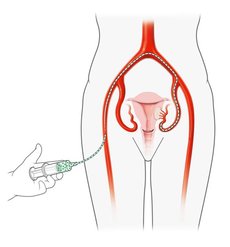

Bei der Embolisation wird über die Leiste ein sehr dünner Schlauch (Katheter) in die Arterie eingeführt und unter Röntgenkontrolle von einem spezialisierten Radiologen bis zur Gebärmutterarterie vorgebracht. Dort werden feinste Kügelchen (Microsphären) in die Myome gespritzt, so dass diese absterben und die Beschwerden verschwinden. Die Gebärmutter selbst bleibt erhalten.